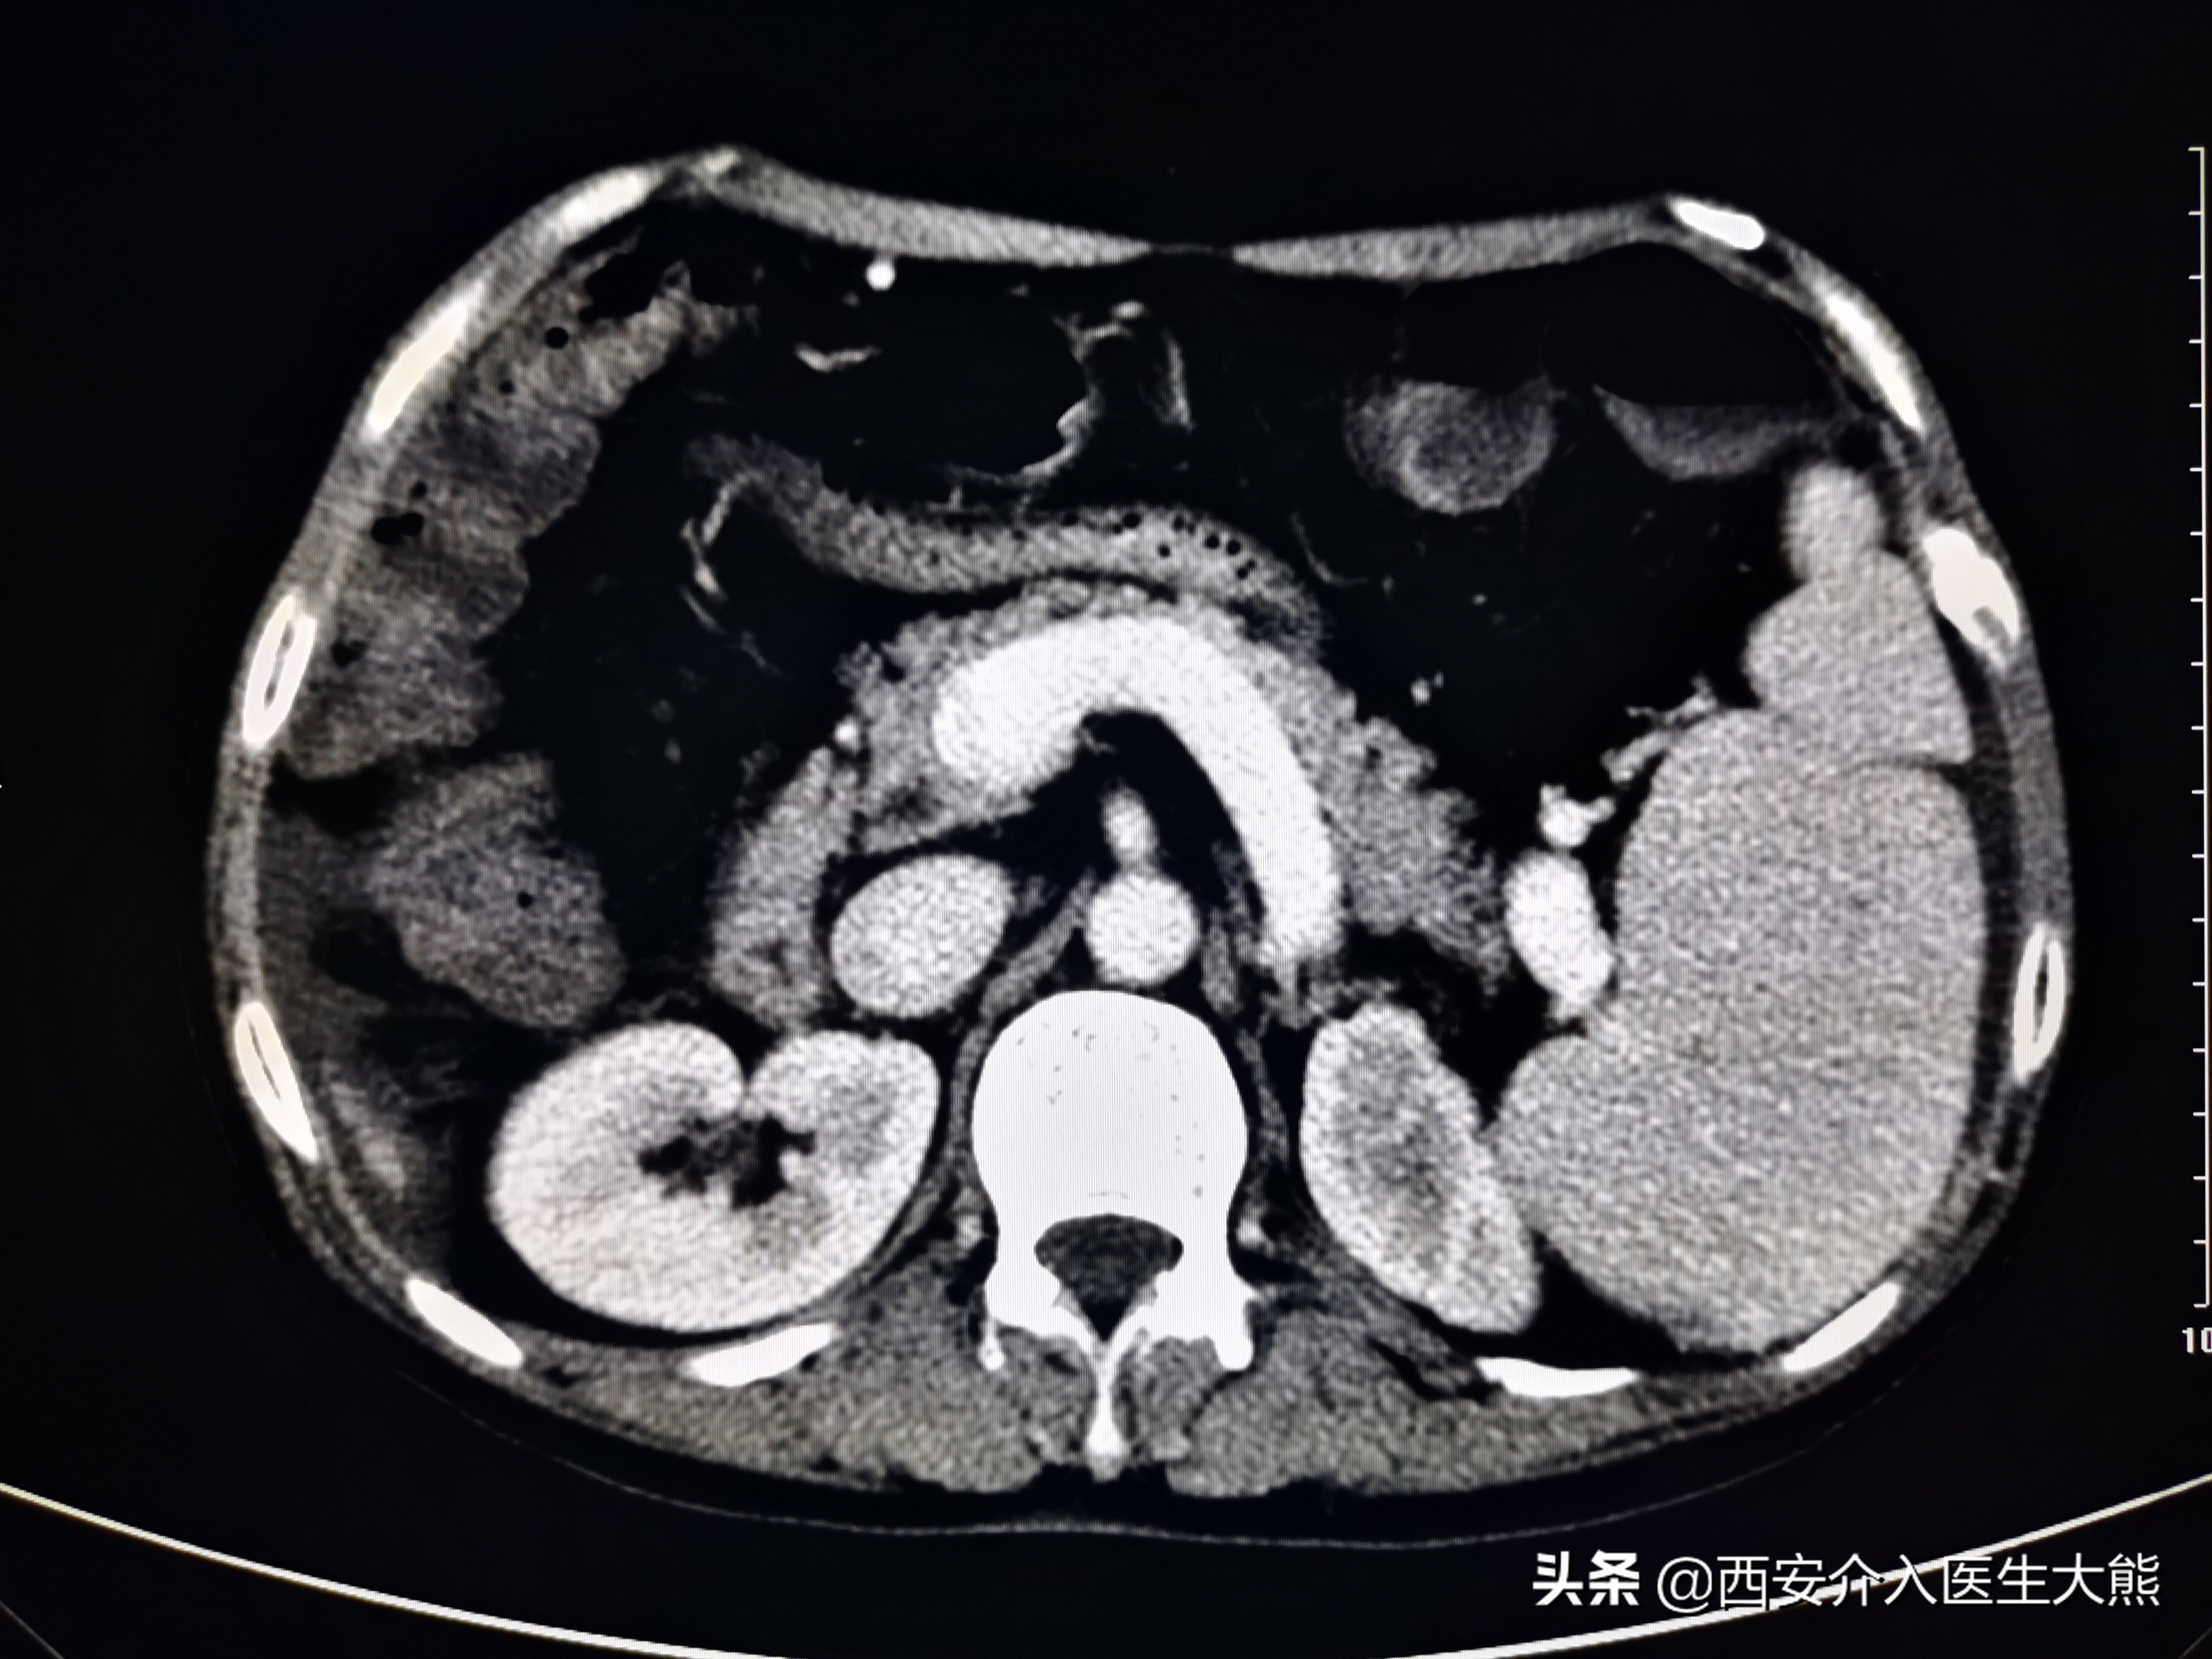

1、CT(2021-11-8):(1)、肝硬化(脾大、门静脉高压、食管胃底静脉曲张,门静脉高压。胆汁淤积,胆囊壁水肿性改变;左肾萎缩,左肾盏结石;(4)、膀胱导尿术后改变;子宫显示不清;直肠CT平扫未见异常。

缩小硬化的肝脏

扩张的脾静脉

扩张的胃底静脉

这名患者的治疗过程就符合该治疗策略。术前的CT平扫已经显示极度扩张的胃冠状静脉,这在DSA影像上得到证实。2018年患者第二次出血时做的增强CT上已经显示出患者的胃冠状静脉扩张。此时,已经具有行TIPS的指征。在经过3年的变化后,病情是急剧加重。如果出血剧烈、生命体征不平稳,或各种原因导致不能行急诊胃镜的情况下,不要错过TIPS降低门脉压力的机会。

胃镜和增强CT是评估患者病情的重要措施。该患者由于病情严重,每一次搬动,都增加了患者再次出血的风险,所以未能完善这2项检查。但是CT平扫的结果证实门静脉及属支的扩张,在某种程度上替代了胃镜的作用。但是不能忽视的是,仍有部分患者可能是消化道溃疡导致出血。根据目前指南的推荐,在病情允许的情况下,应该尽早完善胃镜检查和增强CT。如果病情不允许,普通CT平扫亦能提供部分诊疗信息。